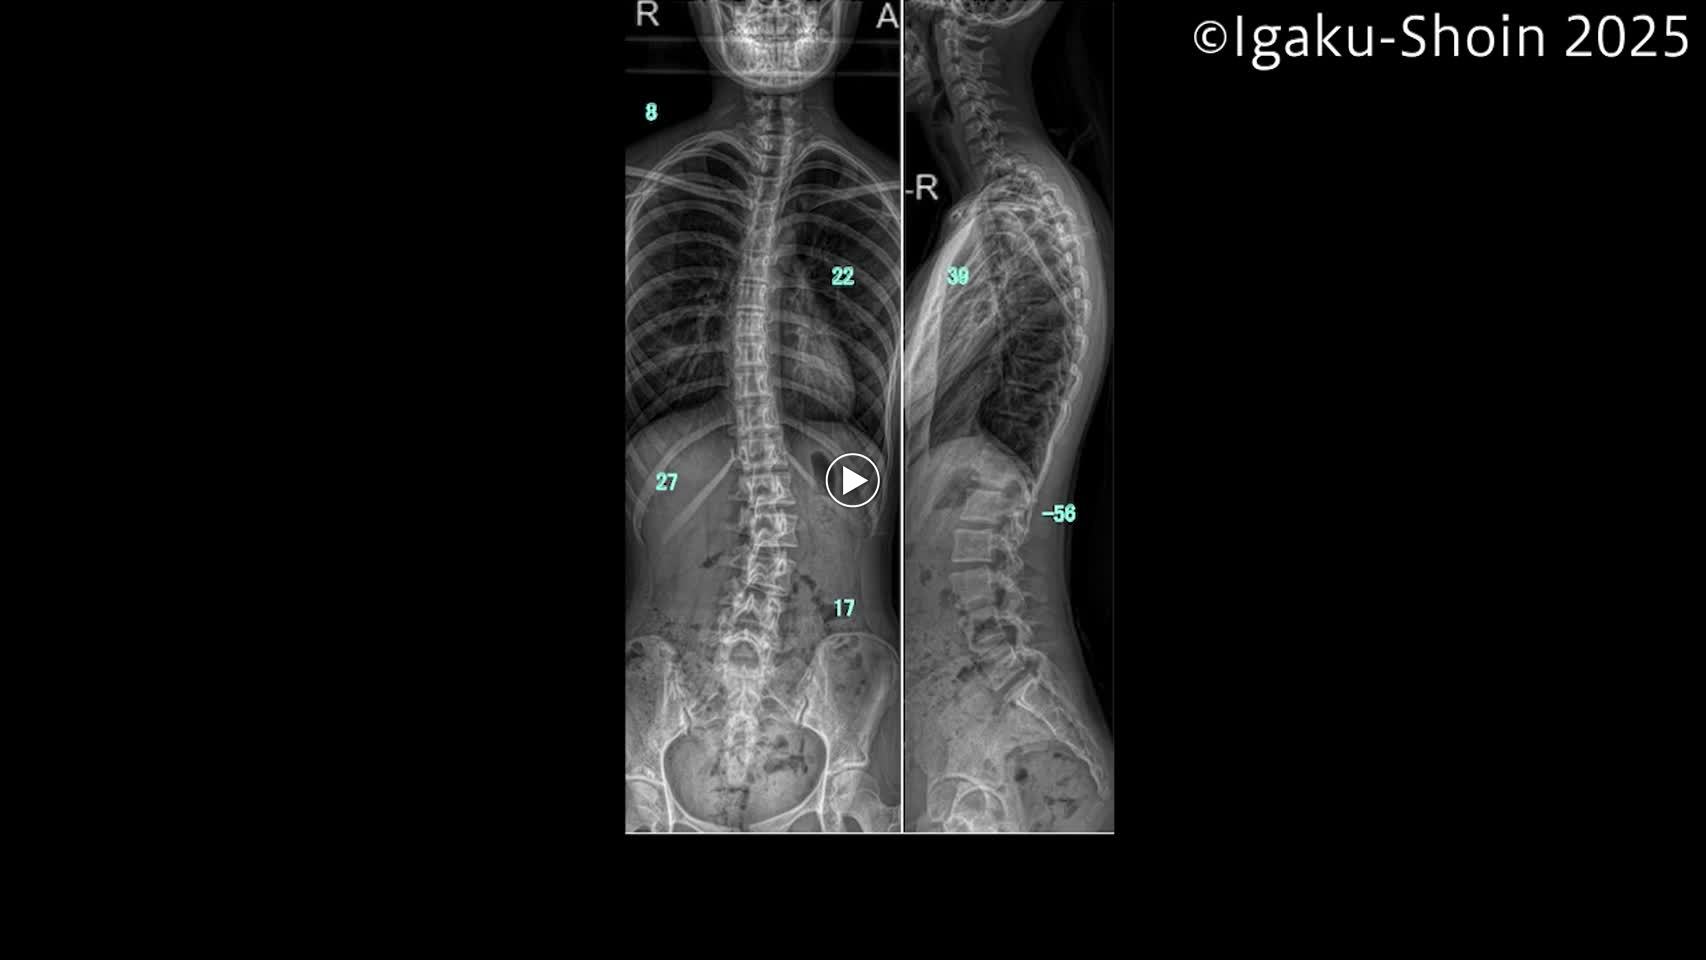

動画37 脊椎外科におけるバイポーラーの使い方

第3章